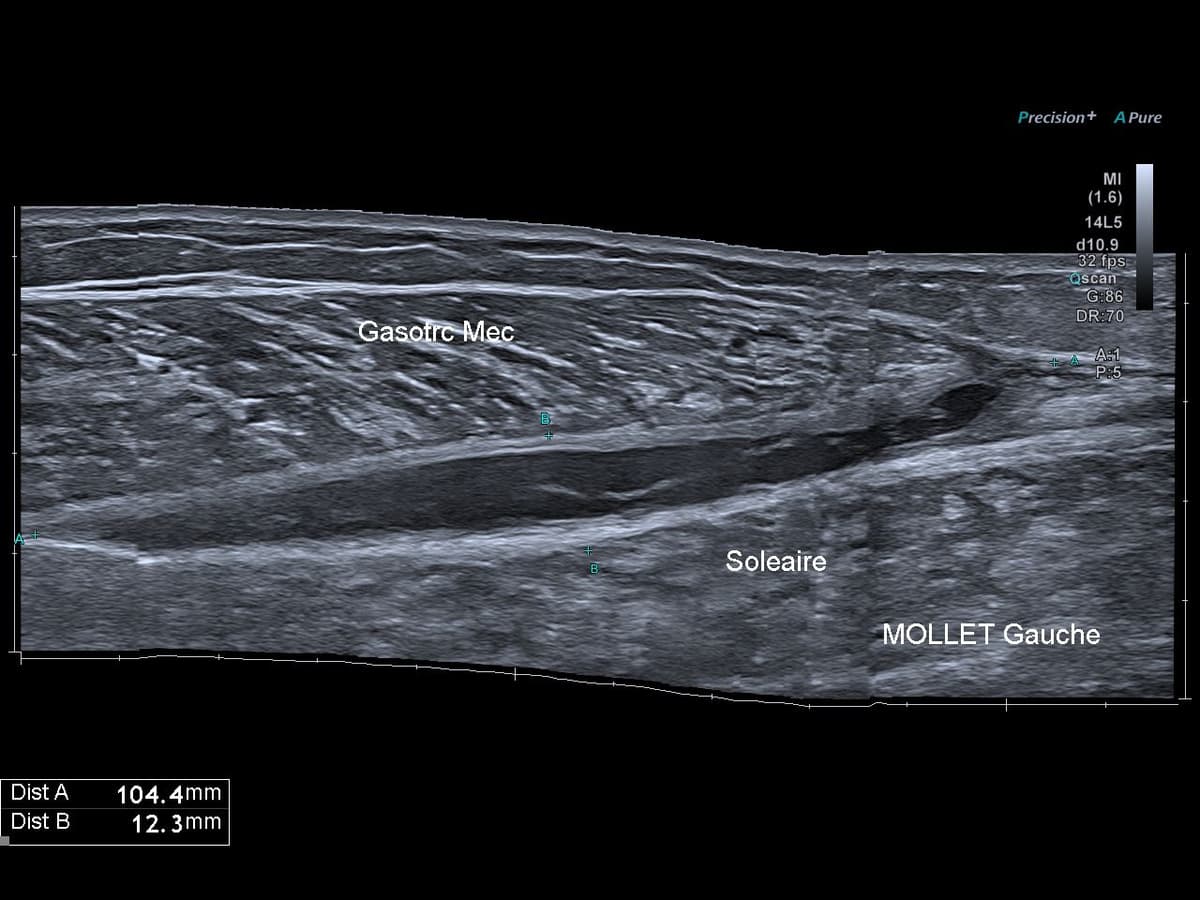

Lesion musculaire de type tennis leg

Evolution cicatricielle d'un tennis leg

Suivi échographique pendant 3 mois de l'évolution d'un tennis leg.